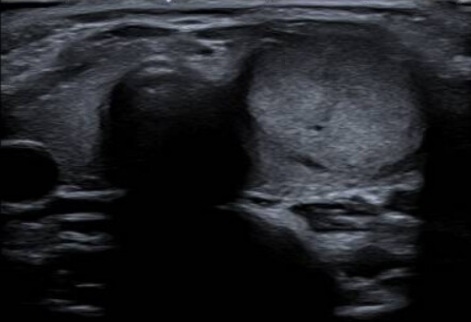

2. ECOGRAFÍA CERVICAL

Ecografía cervical: Lóbulo tiroideo izquierdo aumentado de tamaño a expensas de

imagen nodular sólida, heterogénea, predominantemente isoecoica, sin calcificaciones

y con vascularización desorganizada al examen Doppler color.